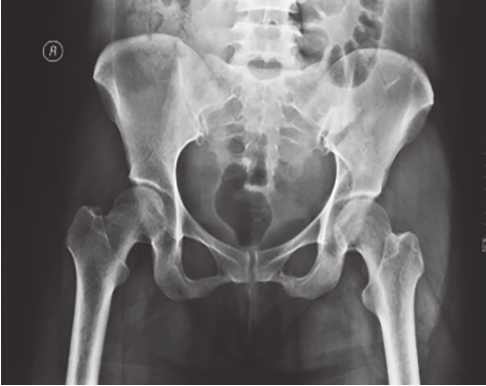

最为常用,患者仰卧,射线呈前后方向垂直投射,骨盆入口边缘与躯干纵轴呈45°~60°夹角。该位像基本能了解骨盆前后环骨折及骶髂关节骨折脱位情况。可用于鉴别骶骨、骨盆髋臼、近端股骨等部位骨折(图2-1)。

图2-1 骨盆前后位X线片

可见左侧骶髂关节骶骨及髂骨面局部骨质断裂,关节间隙增宽,左侧耻上、下支骨折,累及耻骨联合左侧缘。